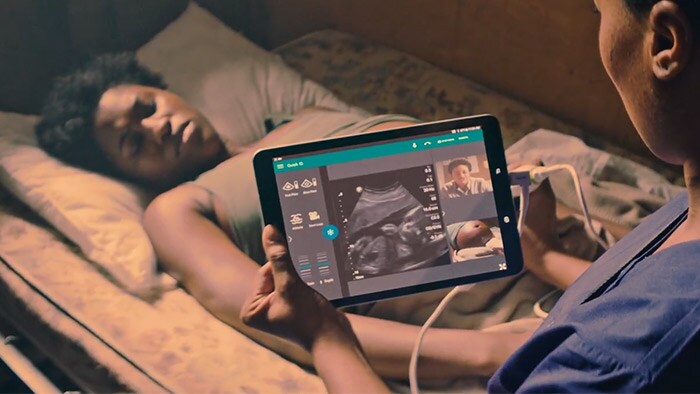

The world's first truly integrated tele-ultrasound solution

Live communications support better, more meaningful collaborations, especially at the moment when needed. Explore how Lumify with integrated Reacts capability brings professionals, places and patients together to make a real difference.